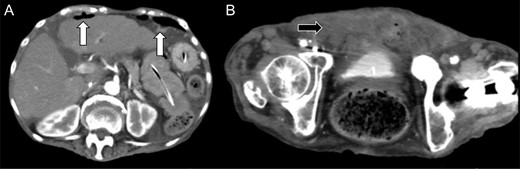

A 76-year-old woman, under the care of a home nurse, had pain on the entire abdomen since the day before presentation to our hospital. She had fever (38.0°C), and her systolic blood pressure dropped to 70 mmHg, and thus, she was referred to our hospital. She was alert and with body temperature of 37.9°C, blood pressure of 83/52 mmHg, heart rate of 103 beats/min, respiratory rate of 30/min, and oxygen saturation of 80% (with 6-L/min mask-to-face ventilation). On physical examination, her abdomen was soft and flat, but she felt tenderness and rebound tenderness on the entire abdomen. Her medical history revealed autoimmune hepatitis controlled with oral steroid, osteoporosis, compression fracture of the spine and spinal canal stenosis, chronic kidney dysfunction, fracture of the left hand and femur, pneumonia, temporomandibular joint myelitis, and cesarean birth with median incision at the lower abdomen. Laboratory test revealed elevation of the inflammation reaction values: white blood cell (WBC), 15 700/μL; C-reactive protein (CRP), 24.0 mg/dL. The blood urine nitrogen (BUN) and serum creatinine values (39.1 and 0.99 mg/dL, respectively) were also elevated. Her urine was purulent and contains rich bacteria (3+) and WBC (3+). Enhanced abdominal computed tomography (CT) showed small intestine dilation, and thus, she was admitted to our hospital with a diagnosis of ileus and septic state, with quick Sequential Organ Failure Assessment Score of 2 points at non-intensive care unit situation (Fig. 1A). An ileus tube was inserted by transnasal endoscopy (Fig. 1B).

(A) Enhanced abdominal computed tomography on admission showing a dilation of the small intestine (white arrow). The patient was diagnosed with ileus state. (B) X-ray of the abdomen revealed an ileus tube and the central venous catheter inserted from the right femoral vein.